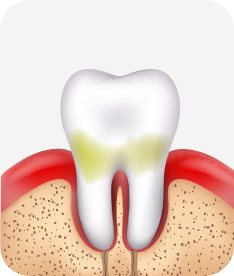

건강한 상태

치아 주위의 잇몸이 핑크색을 띄며, 잇몸에서 피가 나지 않음.

스케일링을 6개월 ~ 1년 주기로 받고 올바른 칫솔질로 건강한 치주 조직을 유지